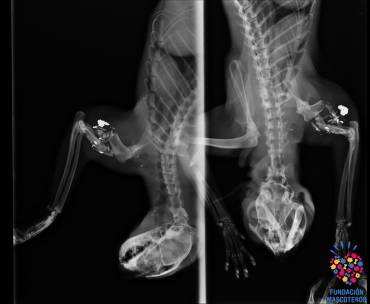

TUNO01 CL El disparo le entró a Tuno por el cuello y le fracturó su pata izquierda.La sorpresa fue cuando en el Centro Veterinario Mascoteros en Rivas-Vaciamadrid hicieron las pruebas radiológicas al gato para valorar qué tipo de fractura sufría y encontraron que tenía el húmero destrozado en pedazos y que además se podía observar en las radiografías restos de un proyectil alojado en su pata. El equipo veterinario se dispuso entonces a buscar la herida del disparo, que fue encontrado en el cuello. Desde la Fundación Mascoteros no es el primer animal que atienden con heridas de disparos, especialmente gatos, pero la familia no daba crédito a lo sucedido con Tuno, conocido y querido por muchos vecinos. Un gato que, según cuentan, no molesta a nadie y mantiene ‘a raya’ a los roedores de la zona a cambio de poder pasearse de vez en cuando por los jardines.

radiografia-gato Imagen de las radiofrafías que se le practicó a Tuno en la Fundación Mascoteros Tuno, tras unos días bajo tratamiento para mejorar la infección de su pata provocada por el destrozo, fue intervenido el pasado 27 de julio por el equipo veterinario de Carlos Rodríguez, un popular veterinario dedicado a la protección animal desde hace casi 30 años y que preside la Fundación Mascoteros. Por su quirófano han pasado miles de animales, muchos de ellos víctimas de atropellos y maltrato de todo tipo, lo que le han convertido en un referente en la cirugía traumatológica.

A pesar de que, en un principio, se dudó si se podía salvar la extremidad de Tuno, finalmente y tras una larga intervención quirúrgica de casi tres horas, se ha conseguido resolver la fractura mediante la instalación de una aguja, una placa y seis tornillos, tras la retirada de los fragmentos óseos y los restos de proyectil. Además, se ha utilizado como injerto tejido óseo del propio animal para evitar rechazo. Las últimas noticias es que Tuno está evolucionando favorablemente, aunque aún es pronto para determinar si recuperará totalmente la movilidad de su pata.